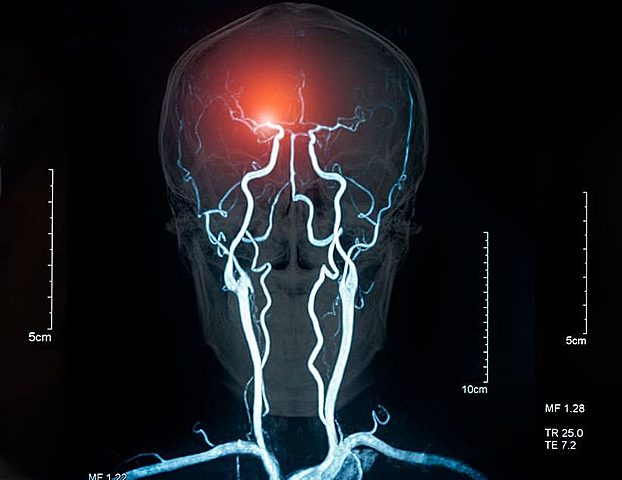

• Identificación de Focos Epilépticos o Tumorales

Identificación de Focos Epilépticos o Tumorales

Wilder Penfild; Creo mapas acerca de la corteza cerebral con el fin de utilizarlos como guía en la realización de las cirugías.

• Equipos Tecnologicos

Equipos Tecnologicos

En la evolución de la ciencia se han creado equipos los cuales pueden evidenciar infinidad de lesiones y/o enfermedades que se tienen sin necesidad de realizar cirugías, se conocen como técnicas no invasivas.

Algunas tecnicas:

Resonancia magnética funcional

Estimulación magnética transcraneal

Electroencefalografía